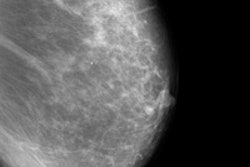

A separate full-field digital mammography (FFDM) study may not be necessary when performing contrast-enhanced digital mammography (CEDM) exams, as the low-energy image may be sufficient for interpretation, according to a new European Journal of Radiology study. This ultimately means a reduction in patient dose.

CEDM uses low-energy (26-30 kVp) and high-energy (45-49 kVp) exposures to produce a subtracted contrast image that highlights sites of contrast enhancement in the breast, according to lead author Dr. Mark Francescone from Columbia University Medical Center in New York. The technique has shown promise for a number of applications, such as screening high-risk women, imaging women with dense breast tissue, and problem-solving in difficult cases.

"Thus, we hypothesized that the presence of iodine in the breast should have no effect on the appearance of the low-energy CEDM image, and that this image should not differ from a standard digital mammogram," they wrote. "Currently, patients undergoing CEDM are required to have standard mammography in addition to the dual-energy examination. However, if the low-energy CEDM image obtained after iodine injection truly is the same as a standard digital mammogram, then these low-energy images could be used as the standard mammogram, thereby reducing radiation dose."

Francescone and his colleagues compared low-energy CEDM images of 170 breasts in 88 women undergoing evaluation for elevated risk or newly diagnosed breast cancer with standard digital mammograms performed within six months. Technical parameters such as posterior nipple line distance, compression thickness, and compression force on the mediolateral oblique (MLO) projection were compared. Mammographic findings were compared qualitatively and quantitatively.

No statistical difference was found in technical parameters such as compression thickness, posterior nipple line distance, or compression force. Neither was there a difference in the measured size of mammographic findings. In terms of grouped calcifications, low-energy contrast images had a mean size/extent of 2.1 cm, and standard FFDM had a mean size/extent of 2.2 cm with equal visibility on both modalities. Masses had a mean size of 1.8 cm in both groups.